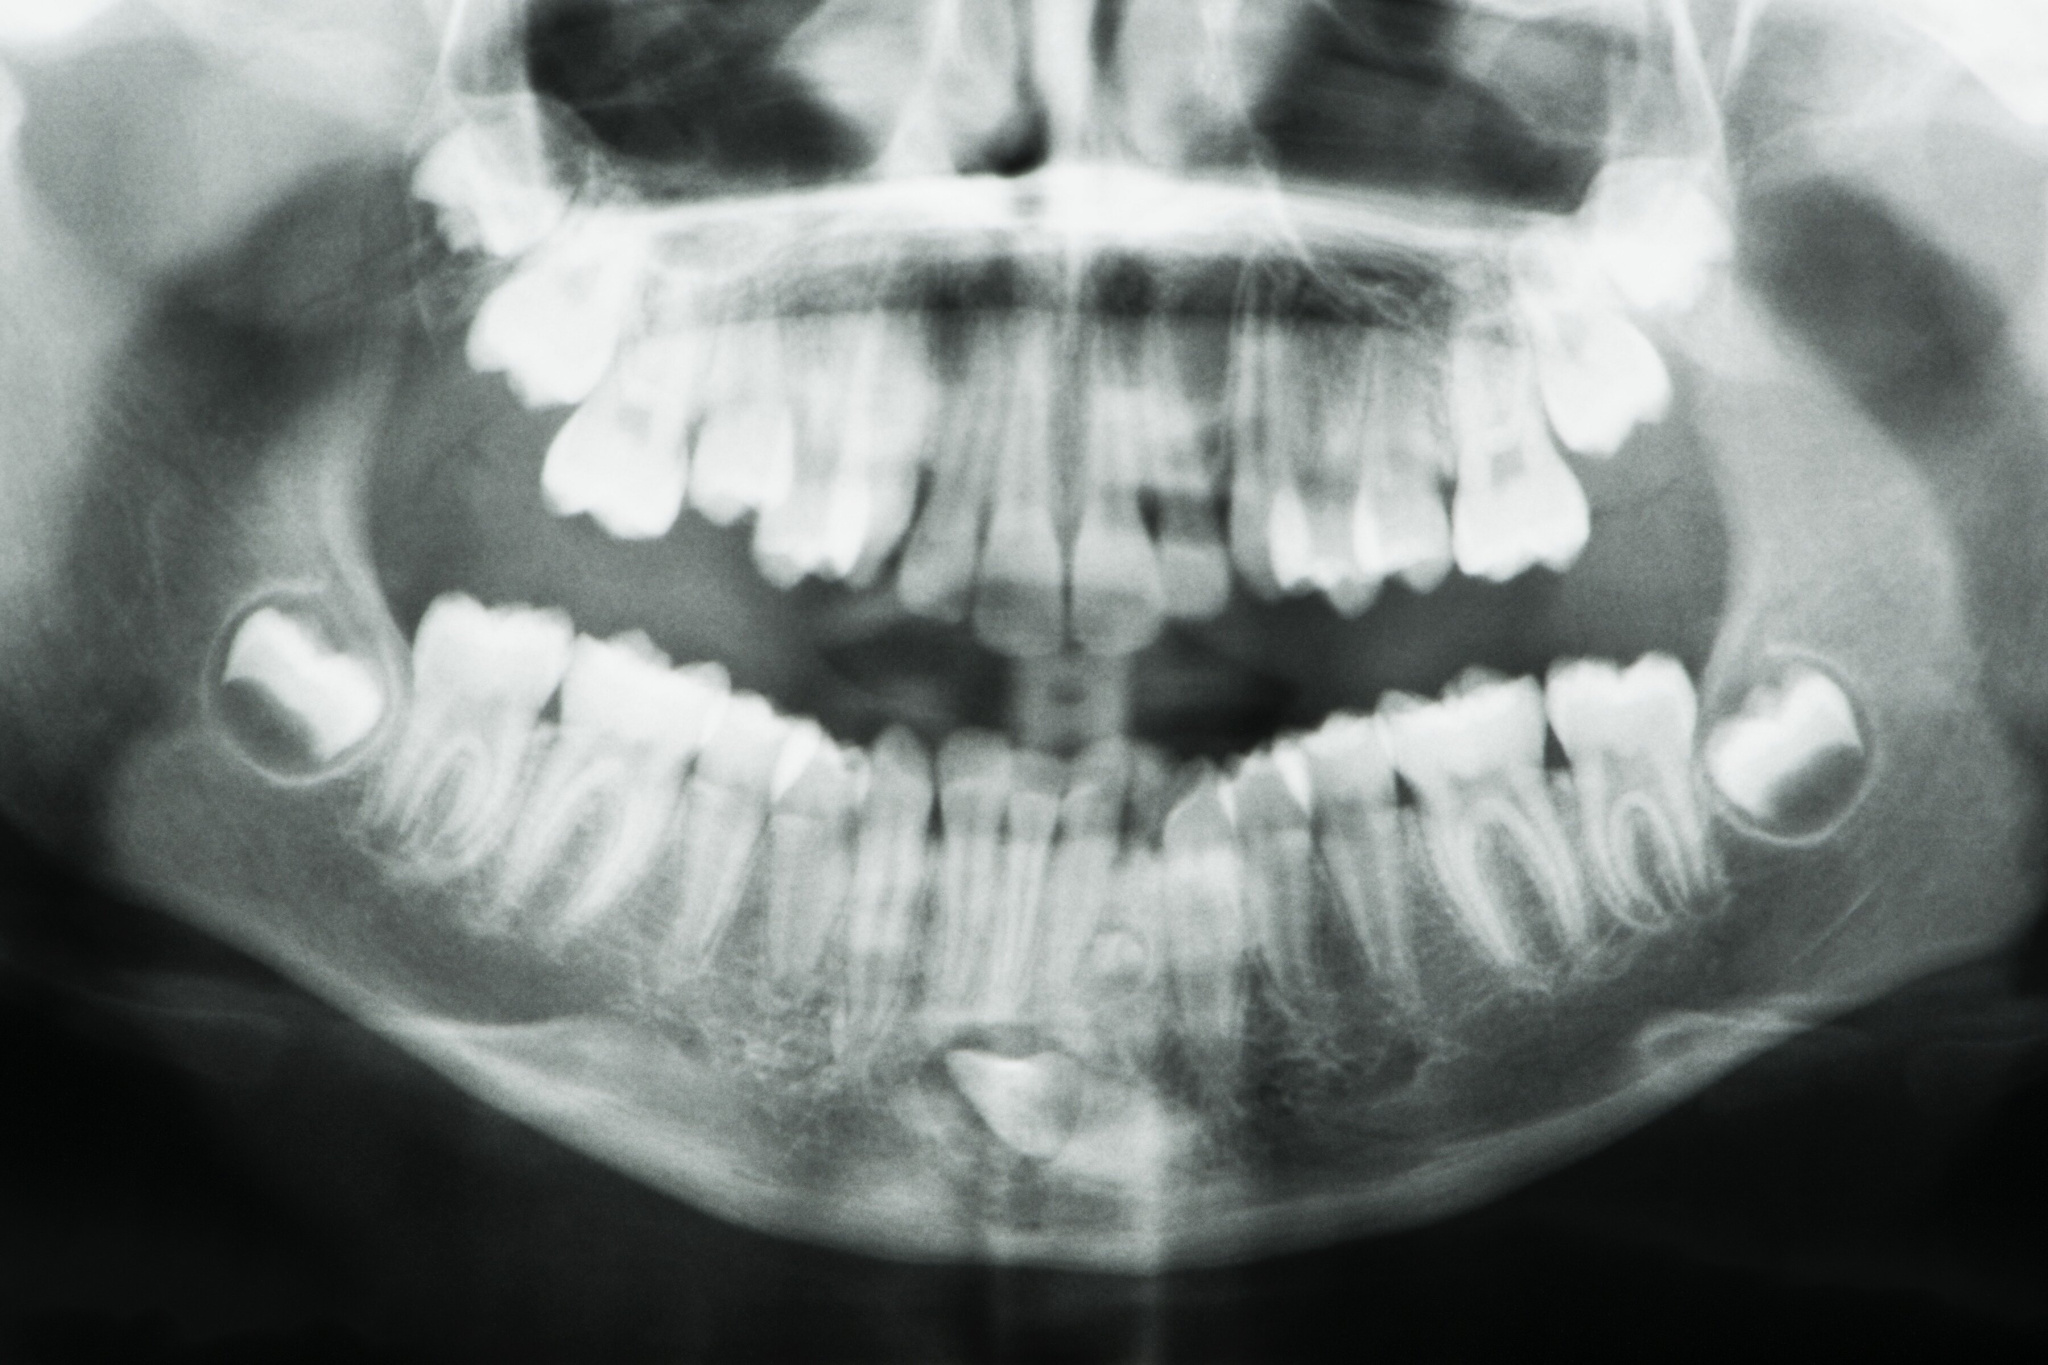

После этого мужчина обратился к стоматологам и сделал рентгеновский снимок. Так оказалось, что в челюсти скрываются еще четыре непрорезавшихся зуба. Когда они полностью появились, общее количество достигло 42. «К счастью, большинство зубов прорезались ровно и без каких-либо осложнений», — отметил Мунианди.